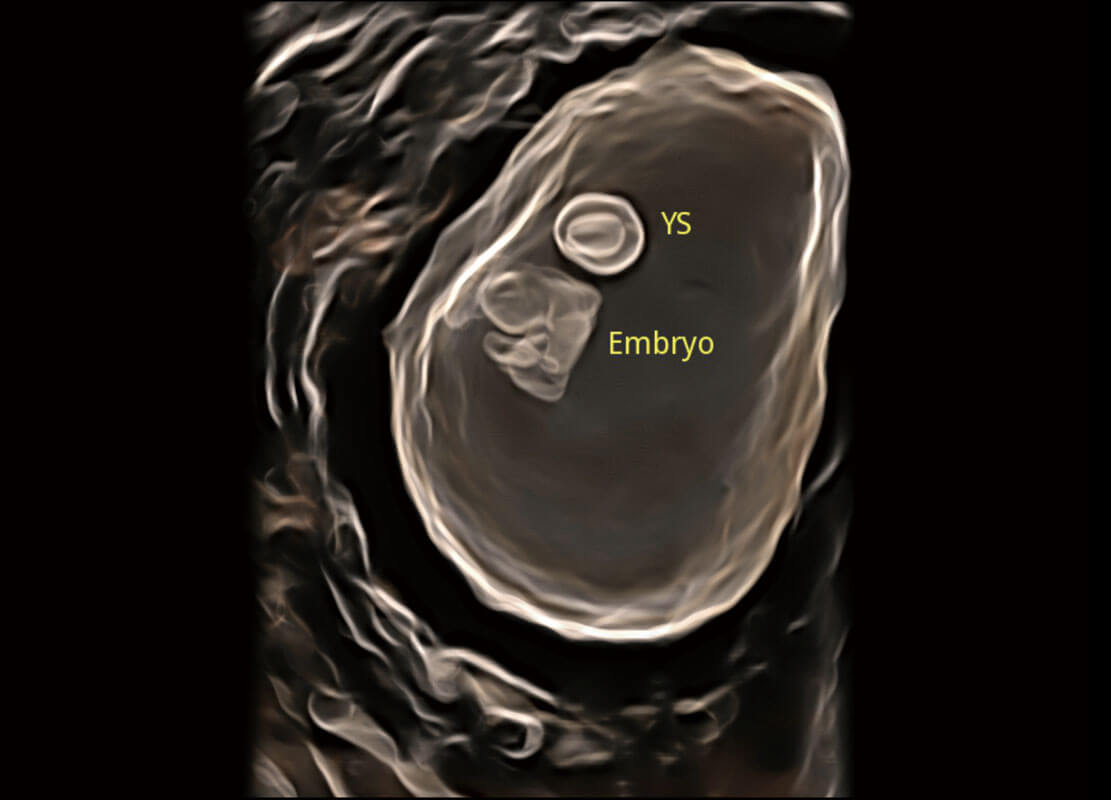

高分辨率容積成像-早孕胎兒

光影成像-孕囊